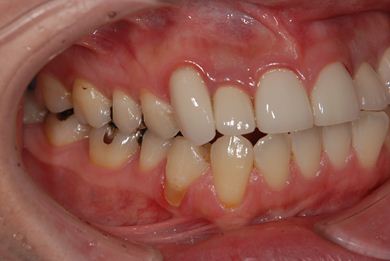

性別/年齢 女性 / 34歳

主訴 前歯2本の黄ばみが気になる。

治療前

• 治療前